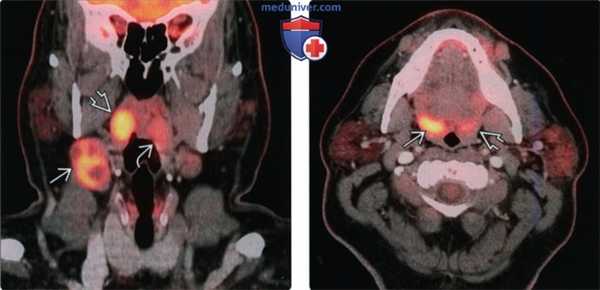

(Слева) При корональной ПЭТ/КТ у пациента с вновь возникшим пальпируемым образованием правой половины шеи определяется повышенное накопление ФДГ в крупном конгломерате лимфоузлов второго уровня, а также асимметричное накопление ФДГ в плоскоклеточном раке правой миндалины. Обратите внимание на отсутствие изменений со стороны левой миндалины.

(Справа) При аксиальной ПЭТ/КТ у этого же пациента определяется несимметрично повышенное накопление ФДГ в правой небной миндалине В по сравнению с противоположной стороной. При КТ с КУ не было обнаружено патологических изменений в этой области. Была выполнена биопсия, подтвердился ПКР.

• ПЭТ/КТ:

о Первичный ВПЧ(+) ПКР и метастазы в лимфоузлах захватывают ФДГ

о Опухоли небольшого размера может быть сложно обнаружить:

- Ткань миндалин в норме также накапливает ФДГ

о Следует остерегаться ложных ФДГ(-) «кистозных» лимфоузлов

о ПЭТ/КТ с КУ лучше всего позволяет оценить первичную опухоль и метастатическую лимфаденопатию

о ПЭТ/КТ с КУ может быть достаточно для поиска первичной опухоли